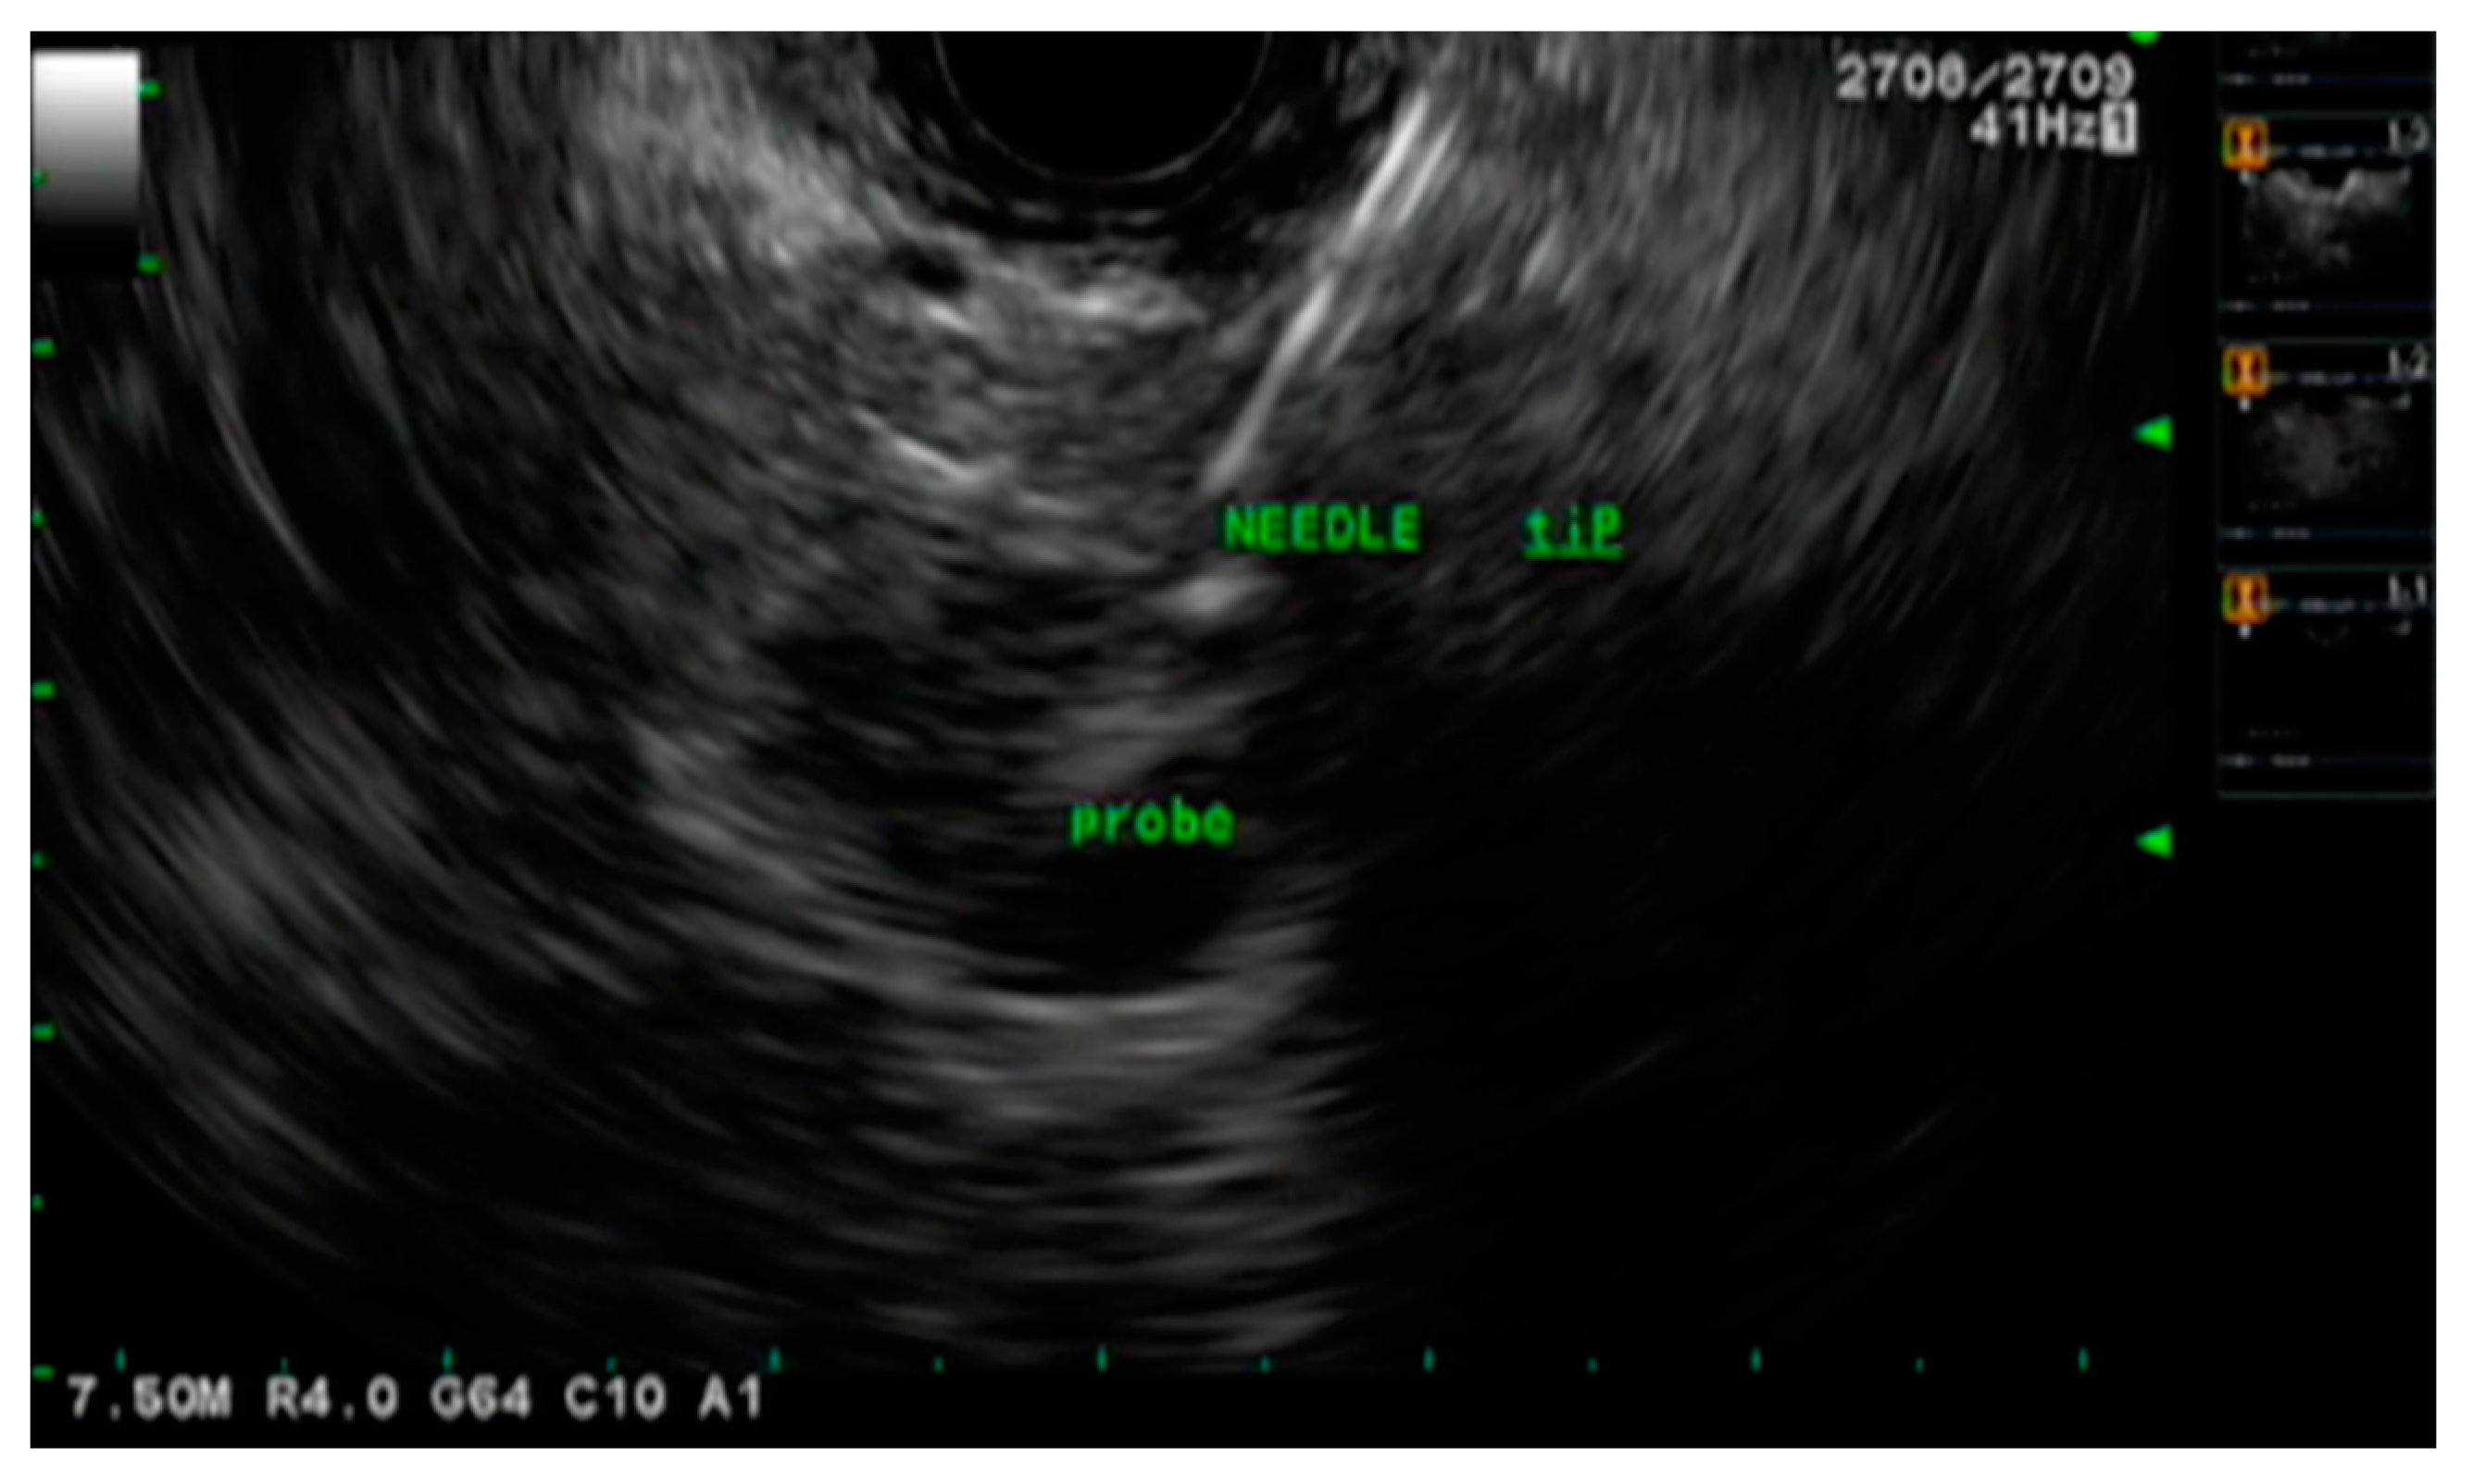

- Goldberg, S.; Mallery, S.; Gazelle, G.; Brugge, W.R. EUS-guided radiofrequency ablation in the pancreas: Results in a porcine model. Gastrointest. Endosc. 1999, 50, 392–401. [Google Scholar] [CrossRef]

- Gaidhane, M.; Smith, I.; Ellen, K.; Gatesman, J.; Habib, N.; Foley, P.; Moskaluk, C.; Kahaleh, M. Endoscopic Ultrasound-Guided Radiofrequency Ablation (EUS-RFA) of the Pancreas in a Porcine Model. Gastroenterol. Res. Pr. 2012, 2012, 1–6. [Google Scholar] [CrossRef] [PubMed]

- Kim, H.J.; Seo, D.-W.; Hassanuddin, A.; Kim, S.-H.; Chae, H.J.; Jang, J.W.; Park, D.H.; Lee, S.S.; Lee, S.-K.; Kim, M.-H. EUS-guided radiofrequency ablation of the porcine pancreas. Gastrointest. Endosc. 2012, 76, 1039–1043. [Google Scholar] [CrossRef]

- Song, T.J.; Seo, D.W.; Lakhtakia, S.; Reddy, N.; Oh, D.W.; Park, D.H.; Lee, S.S.; Lee, S.K.; Kim, M.-H. Initial experience of EUS-guided radiofrequency ablation of unresectable pancreatic cancer. Gastrointest. Endosc. 2015, 83, 440–443. [Google Scholar] [CrossRef]

- Crinò, S.F.; D’Onofrio, M.; Bernardoni, L.; Frulloni, L.; Iannelli, M.; Malleo, G.; Paiella, S.; Larghi, A.; Gabbrielli, A. EUS-guided Radiof-requency Ablation (EUS-RFA) of Solid Pancreatic Neoplasm Using an 18-gauge Needle Electrode: Feasibility, Safety, and Technical Success. J. Gastrointestin. Liver Dis. 2018, 27, 67–72. [Google Scholar] [CrossRef]

- Thosani, N.; Sharma, N.R.; Raijman, I.; Thosani, A.J.; Kannadath, B.S.; Guider, J.C.; Raza, A.; Guha, S. 483 Safety and efficacy of endo-scopic ultrasound guided radiofrequency ablation (EUS-RFA) in the treatment of pancreatic lesions: A multi-center experience. Gastrointest. Endosc. 2018, 87, AB84. [Google Scholar] [CrossRef]